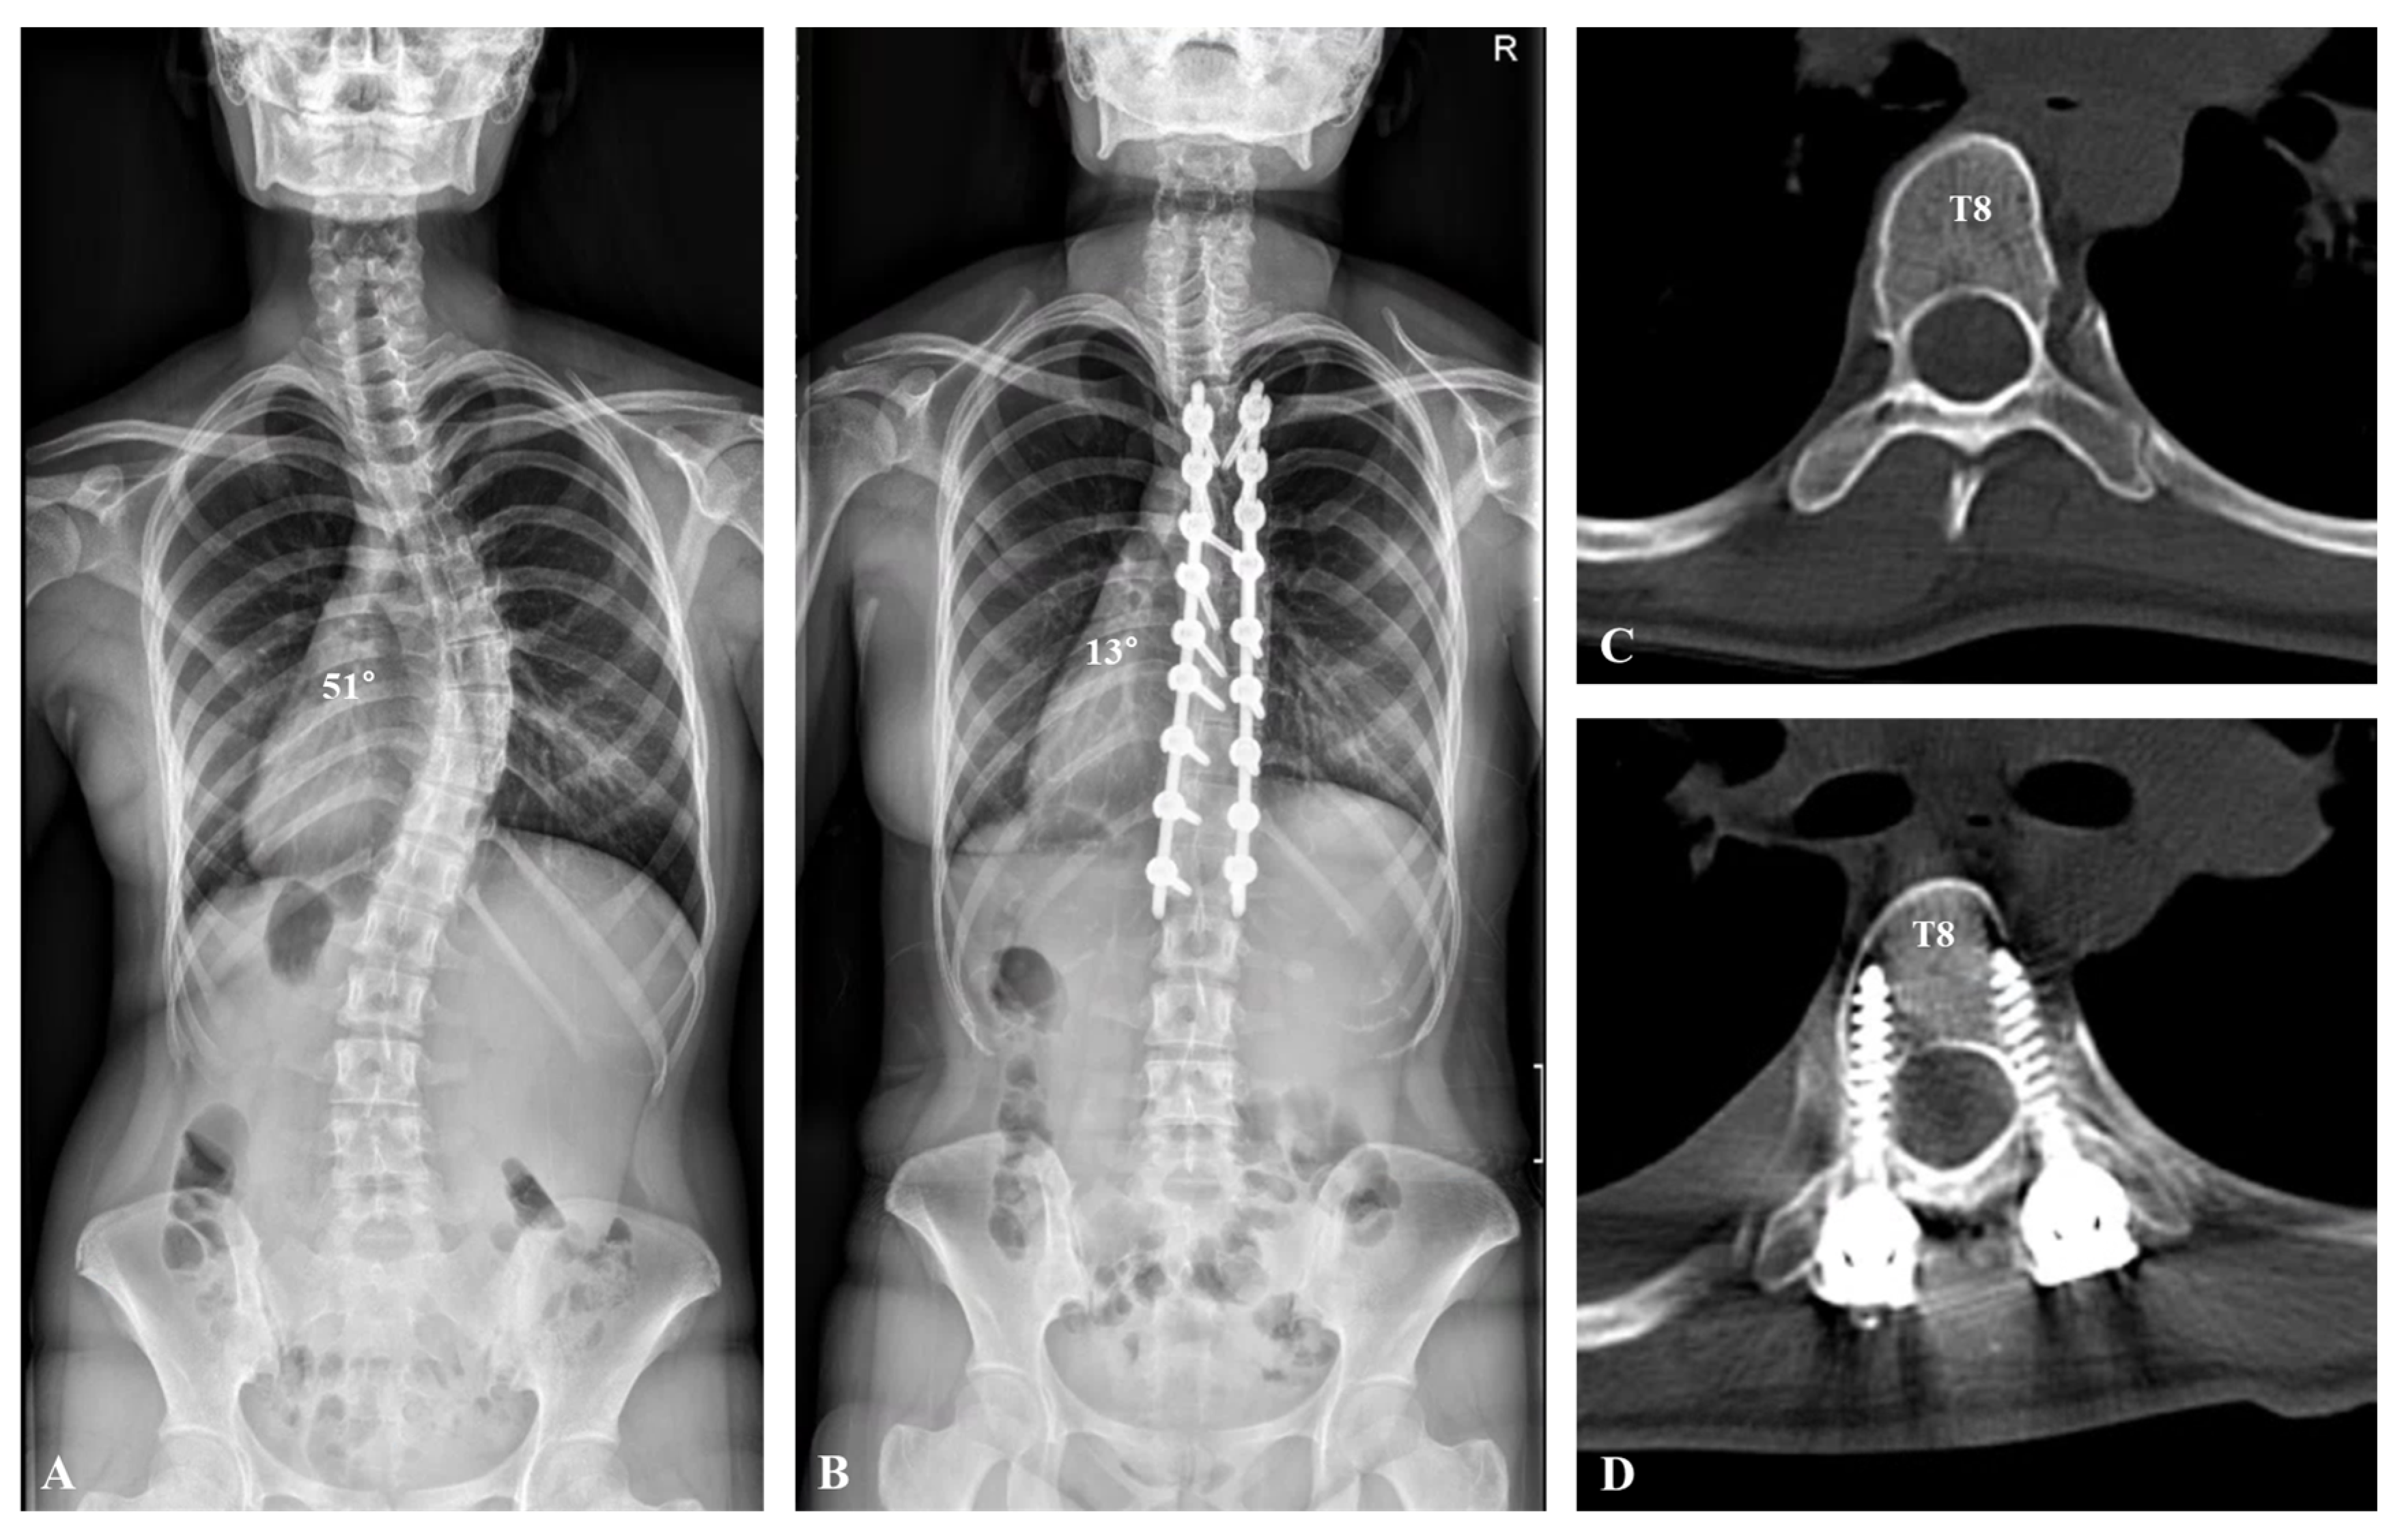

Figure 2.

A 14-year-old female patient visited the hospital for progressive spinal deformity. (A) A whole-spine anteroposterior image showed 51° of scoliosis deformity with T8 apical vertebra. (B) Deformity correction from T5 to L1 was performed with polyaxial pedicle screws and rod derotation, resulting in a correction from 51° to 13°. (C,D) Axial view of computed tomography presented the apical vertebra (T8) before and after deformity correction.